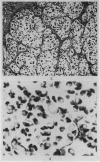

Heterotransplantation of a human colonic neoplasm with classical morphologic characteristics of a carcinoid was sucessful in the cheek pouches of unconditioned, adult golden hamsters after a short sojourn in cell-impermeable chambers in rats. Although no mucin-secreting cells were detected in the donor carcinoid, the cheek pouch transplants exclusively exhibited mucinsecreting tumour cells of signet-ring type consistent with adenocarcinoma. This transplantable tumour, designated GW-77, has retained this appearance as well as expansive growth characteristics in xenogeneic hosts for a period of 4 years.

These findings represent strong biological evidence consonant with views, based upon morphological findings, advocating a histogenetic relationship between colonic carcinoid and adenocarcinoma. It is believed that colonic adenocarcinoma has a selective advantage over carcinoid for serial propagation in an alien environment, indicating the less differentiated nature of its cellular components. Since the donor carcinoid cells failed to exhibit argentaffin reactions, these conclusions may be limited only to the nonreactive forms of carcinoid.